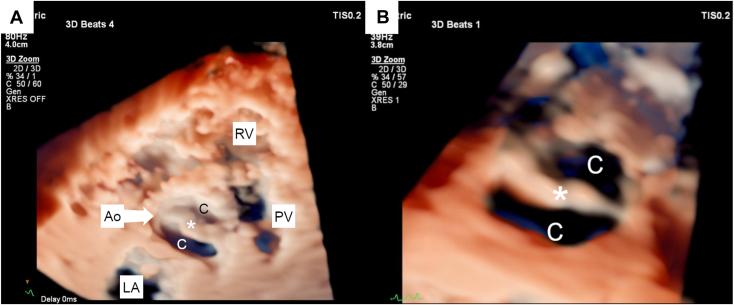

Bicuspid Aortic Valve in a Healthy Cat: Two- and Three-Dimensional Assessment.

• BAVs can be encountered in cats without clinical signs. • A BAV appeared to be an isolated cardiac abnormality in this cat. • 3D TTE can be successfully used in cats to characterize the aortic valve.

摘要

• 猫可能出现二叶式主动脉瓣(BAV)但无临床症状。

• 这只猫的二叶式主动脉瓣似乎是一种孤立的心脏异常。

• 三维经胸超声心动图(3D TTE)可成功用于猫以对主动脉瓣进行特征描述。